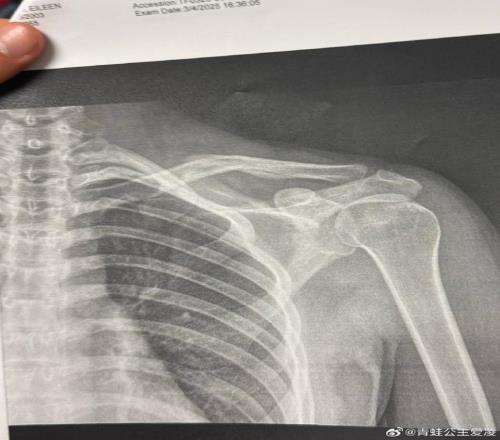

2025年3月9日,谷愛凌在社交網(wǎng)絡上發(fā)布了一張X光片。 但事實是,谷愛凌確實在這個奧運周期的最后沖刺階段不停經(jīng)歷著傷病的折磨。2025年3月9日,谷愛凌在社交網(wǎng)絡上發(fā)布了一張X光片。圖片上,她右側鎖骨的裂縫清晰可見,配文只有一個心碎的表情符號,而這僅僅是“職業(yè)生涯最艱難一年”的開始。 那一年初,谷愛凌在美國阿斯本的嚴重摔傷,讓她被迫離開賽場兩個月,直到4月份她才開啟身體的恢復進程,從小心翼翼的康復訓練起步,慢慢積攢重返賽場的力量。然而,當谷愛凌在8月份到新西蘭訓練時,她再次受傷,因一次意外碰撞導致腰部神經(jīng)損傷。重重打擊下,她的賽季首秀并不順利,2025年11月的斯圖拜坡面障礙技巧世界杯,傷愈復出的她狀態(tài)遠未調整到位,在嘗試新動作時出現(xiàn)失誤,僅名列第29位,未能晉級決賽。國際雪聯(lián)的世界杯積分榜上,她的名字一度滑落。一時間,外界對她的冬奧前景充滿了疑問。 “其實奧運年是和其他三年非常不同的一年。因為所有人的壓力都非常大,因為所有人都會有突破性的滑行或者新動作,但是也有很多我非??粗氐倪\動員都受傷了,這也嚇著我了,所以我也希望能夠順利到達目的地,這就是很大的目標之一,因為只有到了那里(米蘭)才能算開始。”